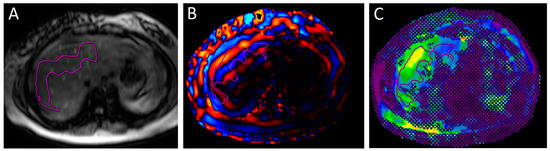

2.2. Assessment of Fibrosis and Steatosis

- Furlan, A.; Tublin, M.E.; Yu, L.; Chopra, K.B.; Lippello, A.; Behari, J. Comparison of 2D Shear Wave Elastography, Transient Elastography, and MR Elastography for the Diagnosis of Fibrosis in Patients With Nonalcoholic Fatty Liver Disease. AJR Am. J. Roentgenol. 2020, 214, W20–W26. [Google Scholar] [CrossRef]

- Loomba, R.; Wolfson, T.; Ang, B.; Hooker, J.; Behling, C.; Peterson, M.; Valasek, M.; Lin, G.; Brenner, D.; Gamst, A.; et al. Magnetic resonance elastography predicts advanced fibrosis in patients with nonalcoholic fatty liver disease: A prospective study. Hepatology 2014, 60, 1920–1928. [Google Scholar] [CrossRef]

- Selvaraj, E.A.; Mózes, F.E.; Jayaswal, A.N.A.; Zafarmand, M.H.; Vali, Y.; Lee, J.A.; Levick, C.K.; Young, L.A.J.; Palaniyappan, N.; Liu, C.H.; et al. Diagnostic accuracy of elastography and magnetic resonance imaging in patients with NAFLD: A systematic review and meta-analysis. J. Hepatol. 2021, 75, 770–785. [Google Scholar] [CrossRef]